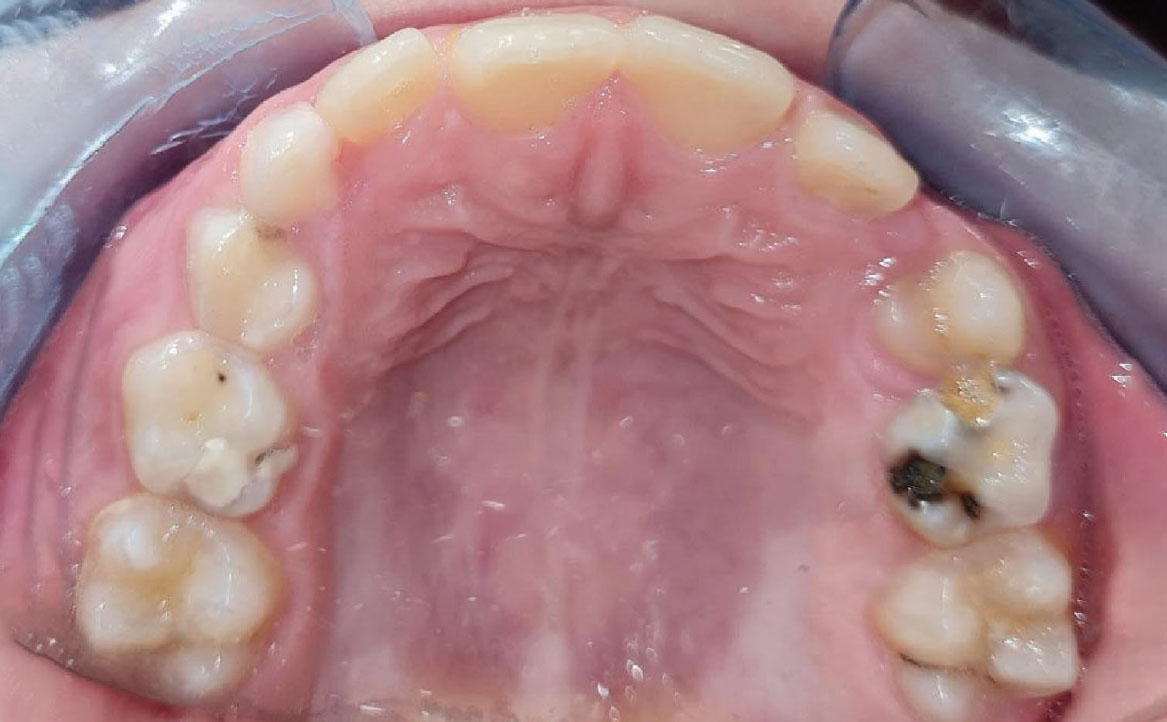

L’overjet e l’overbite sono entrambi ridotti in massima intercuspidazione. Trasversalmente il mascellare superiore è contratto (fig. 4-7).

Fig. 6A Foto dell'arcata superiore.

Fig. 6B Modello digitale dell'arcata superiore.